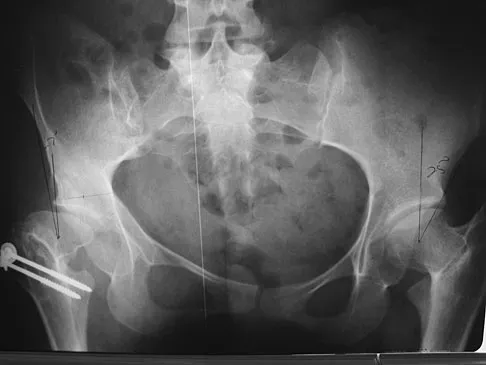

Figures 22a and 22b show the radiographs of a patient who reports stiffness of the hip and associated pain. Management should consist of

The patient has grade IV heterotopic ossification with the limb in an abnormal nonfunctional position. Treatment should consist of excision of the bone to restore hip motion and prophylaxis to prevent recurrent formation. The best time to excise the bone is controversial, with no conclusive evidence supporting early or late excision. Pellegrini VD Jr, Koniski AA, Gastel JA, Rubin P, Evarts CM: Prevention of heterotopic ossification with irradiation after total hip arthroplasty: Radiation therapy with a single dose of eight hundred centigray administered to a limited field. J Bone Joint Surg Am 1992;74:186-200.

- Warren SB, Brooker AF Jr: Excision of heterotopic bone followed by irradiation after total hip arthroplasty. J Bone Joint Surg Am 1992;74:201-210.